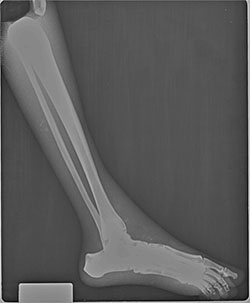

BREAK-APART PIXY Hands X-Ray BREAK-APART PIXY Legs X-Ray 1 BREAK-APART PIXY Legs X-Ray 2 BREAK-APART PIXY Torso X-Ray